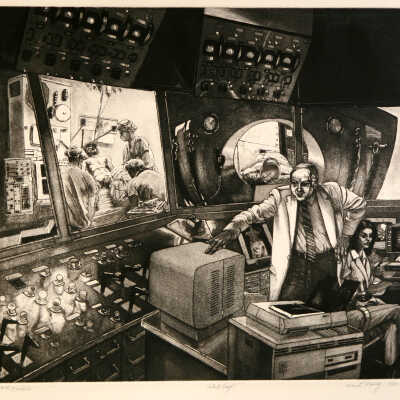

By-Pass Study C.A.T. Scanner

C.I.S. #85 CAT Scanner